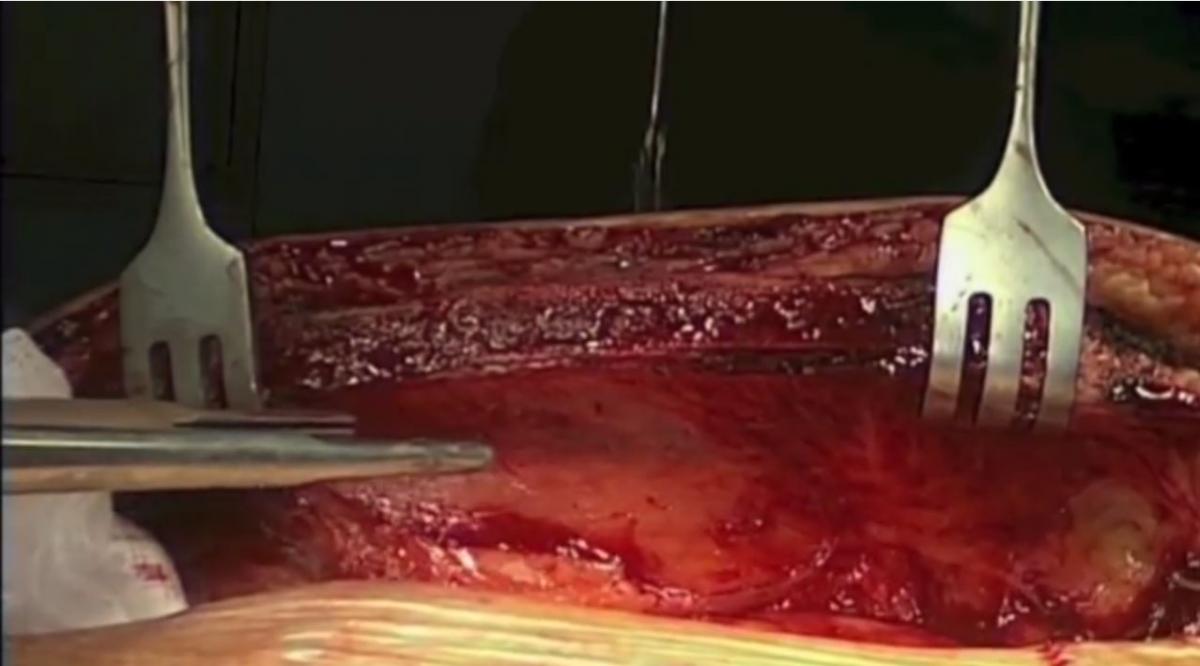

2. ITA Harvest: Simplified Step-by-Step Approach Ahmed Ouda Tamer Ghazy Klaus Matschke Utz Kappert |